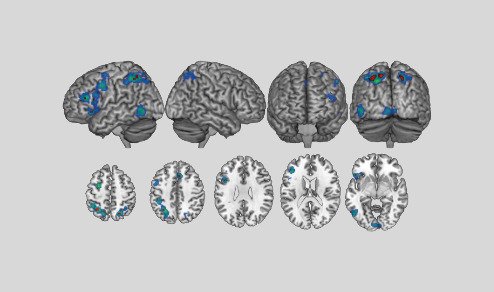

Este año, los científicos han descubierto que al ‘alternar’ las frecuencias en un patrón fractal, se consigue emular el ciclo de la naturaleza al crear nuevas conexiones neuronales, estimulando con éxito la corteza prefrontal.

Mediante una fusión de los efectos de sincronización hemisferial y neuronal.

Sincronización Hemisferial + Neuronal = Activación Prefrontal

Resultado: Capacidad de Cognición Optimizada

▪️▫️▫️ Capa 1 de 3:

Tecnología Interaural de Sincronización Hemisferial

Conecta Ambos Hemisferios

La primera capa de la tecnología HybridWave™ potencia este fenómeno.

Gracias a su tecnología de diferencia interaural, se logra sincronización hemisferial.

Sincronizando tus ondas cerebrales entre hemisferios para liberar tu máximo potencial cognitivo.

Como Da Vinci, puedes activar la intuición del hemisferio derecho y la lógica del izquierdo en perfecta armonía, accediendo a una inteligencia más profunda y multidimensional.

▪️▪️▫️ Capa 2 de 3:

Tecnología Isocrónica de Activación Neuronal

Activa tu Potencial Neuronal

La segunda capa de la frecuencia híbrida, impulsada por HybridWave™.

Utiliza pulsos isocrónicos para inducir un estado de sincronización neuronal profunda.

Afinando el ritmo y la vibración de la actividad eléctrica de tu cerebro por medio de la frecuencia.

Esto optimiza tu enfoque, y desbloquea un estado de alto rendimiento mental.

▪️▪️▪️ Capa 3 de 3:

Tecnología Fractal de Activación Prefrontal

Despierta tu Súpercerebro

HybridWave™ amplifica la activación del Neocórtex.

Gracias a su tercera capa de tecnología-fractal de activación prefrontal.

Amplifica la neuroplasticidad, mejorando la capacidad de aprender y adaptarse en tiempo real.

Al fusionar los efectos de sincronización hemisferial y neuronal, con la activación prefrontal,

accedes a un nivel de pensamiento reservado para los genios.

Sincronización Hemisferial + Activación Prefrontal + Sincronización Neuronal = Capacidad de Cognición Optimizada